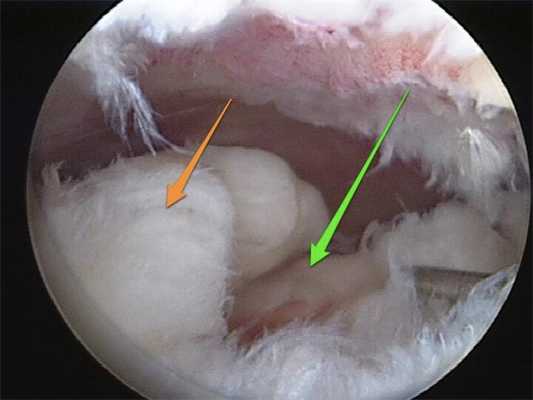

в) Основным показанием к хирургическому лечению при свежем вывихе надколенника является необходимость коррекции сопутствующих проблем (значительного размера внутрисуставное тело, разрыв мениска). В редких случаях вывих надколенника является невправимым закрыто или имеет место его выраженная нестабильность после вправления

• На аксиальной рентгенограмме на рис. 2 видно свободное внутрисуставное тело в области латерального заворота коленного сустава после вывиха надколенника. Обратите внимание на дефект медиальной фасетки надколенника

• На аксиальной МР-томограмме (рис. 6) видны признаки отрыва МБНС в области ее прикрепления к бедренной кости.